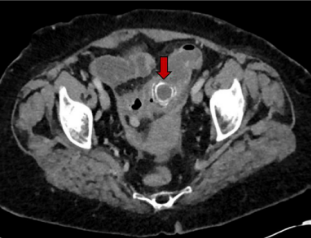

抽血检查发现患者炎性标记物升高,白细胞计数15.6x109,C反应蛋白(CRP)为67mg/L,肝功能中胆红素,碱性磷酸酶,谷丙转氨酶等均升高,提示肝功能异常,有梗阻性黄疸可能。腹部CT检查发现十二指肠近端和结肠远端分别两块结石,大小约3cm和3.3cm(如图1和图2);同时报告了胆囊结石伴急性胆囊炎,胆总管扩张,约1.7cm,验证了胆囊结石引起的Bouveret综合征。

图2 乙状结肠梗阻,梗阻原因为结石嵌顿